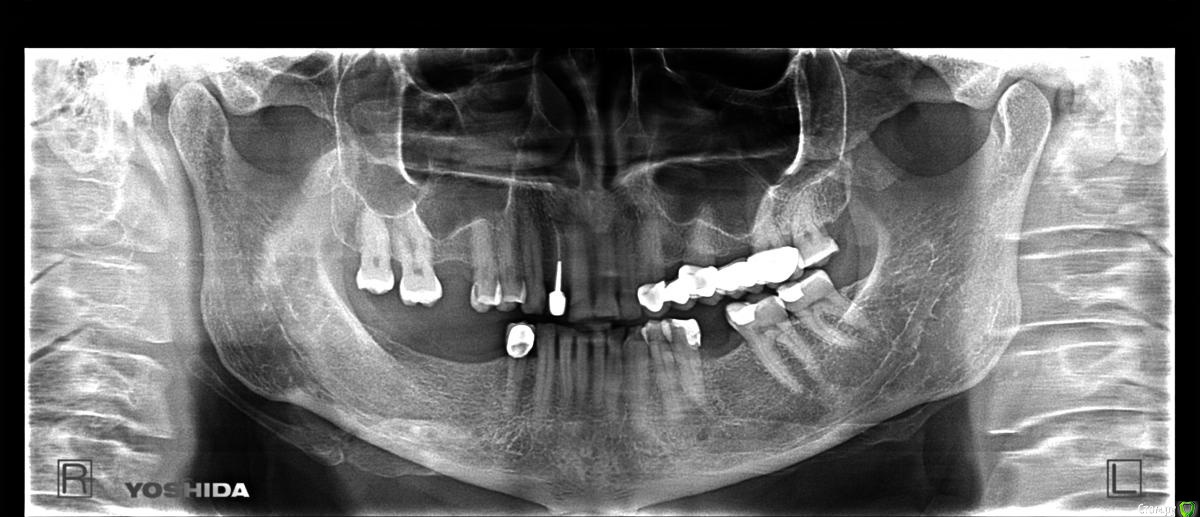

alekcandr ovs. Опубликовано 1 ноября, 2016 Автор Поделиться Опубликовано 1 ноября, 2016 Фото моделей в привычной окклюзии бы посмотреть,там место справа есть под коронки на имплантах?Что вас конкретно смущает?· Мама в другом городе,только ОПТг пока скинула. Хочет приехать ко мне на праздники,я в свою очередь хочу начать протезиро...Планирую установить имплантаты в область 16,45,46,47 зубов первый этап запротезировать Потом перейти на левую, имплант 36,верхний мост пока трогать не буду. Вопросы 1.Как бы Вы протезировали ????импланты Астра или Нобель?? 2.протезирование,Все на индивид….абатменах или стандарт, коронки циркон или E/max или М.К ??? Хочу сделать маме как наилучше. Спасибо Ссылка на комментарий

krokomot Опубликовано 1 ноября, 2016 Поделиться Опубликовано 1 ноября, 2016 1.6 иплантат закрытый синус, 3.6, 4.5,4.6,4.7, все на индивидуальных абатментах с винтовой фиксацией, почему именно астра-нобель, прикидочно на расходники на астре у вас только 130 тыр уйдет, это учитывая то что набор вы возьмете в аренду плюс работа техников и протезирование примерно 80 тыров это чистыми. итого больше 200 это только вам как врачу отдать надо можно присмотреться к более бюджетным системам если что)), астра конечно гуд но...$ . Фиксацию делаю в основном только винтовую. для жевательной группы вполне достаточно метал-керамика. Ссылка на комментарий

колесников Опубликовано 1 ноября, 2016 Поделиться Опубликовано 1 ноября, 2016 Попросите сделать кт . Вероятно в 4ом сегменте узкий гребень. Если так,я бы "своему" пациенту предложил анкилос (если по высоте проходит). Менее травматично выйдет. Сразу формирователи и сст. 16 закрытый синус и только астра,4.5х9 конус. 17 дистализация и ортодонтическая экструзия (можно и под коронку,но это не наш метод). 37 вкладка. Ссылка на комментарий